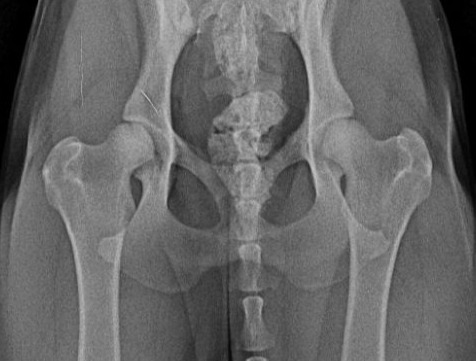

Dépistage de la dysplasie de hanches

Dysplasie des hanches

Explications et point sur les denieres avancées en connaissances des origines, mécanismes, et traitements de la pathologie. Article du Dr Jean-Marc Wurtz, 2022.